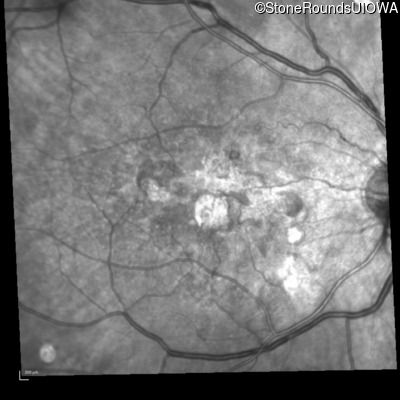

Infrared Fundus Photograph - Right - 20/80 -1

Exemplar